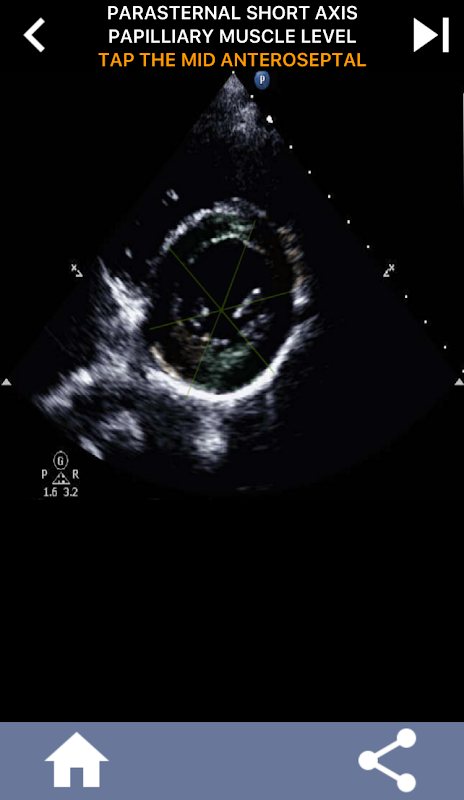

AHA دل کے حصوں کو سیکھنے کے لئے کوئز پر مبنی بصری نقطہ نظر: ایکو کارڈیوگرافی۔

AHA (امریکن ہارٹ ایسوسی ایشن) کے دل کے حصوں کو سمجھنا کارڈیک سونوگرافر کے لیے انتہائی اہمیت کا حامل ہے تاکہ وہ رپورٹ لکھنے والے ماہر امراض قلب کے ساتھ مؤثر طریقے سے بات چیت کر سکے۔ مخصوص جسمانی خطوں اور ان کے متعلقہ حصوں کو جان کر، سونوگرافر کسی بھی غیر معمولی باتوں یا نتائج کو درست طریقے سے بیان اور بات چیت کرسکتا ہے، دونوں پیشہ ور افراد کے درمیان واضح اور جامع مواصلت کو یقینی بناتا ہے۔

یہ تفہیم خاص طور پر اس وقت اہم ہو جاتی ہے جب ماہر امراض قلب کسی مسئلے کے صحیح محل وقوع کا پتہ لگانے کی کوشش کرتا ہے یا جب کال پر ڈاکٹر کسی مخصوص علاقے میں کسی مسئلے کی نشاندہی کرتا ہے، سونوگرافر کو متعلقہ طبقہ کو درست طریقے سے ظاہر کرنے کا اشارہ کرتا ہے، جیسے کہ درمیانی کمتر دیوار۔ اس طرح، AHA دل کے حصوں کی ایک جامع گرفت کا حامل ہونا ضروری مہارت کا مجموعہ ہے۔

یہ ایپ اصل ایکو امیجز کا استعمال کرتے ہوئے آپ کے علم کی جانچ کرے گی، جو مجھے اکثر پڑھانے کا بہترین طریقہ معلوم ہوتا ہے۔